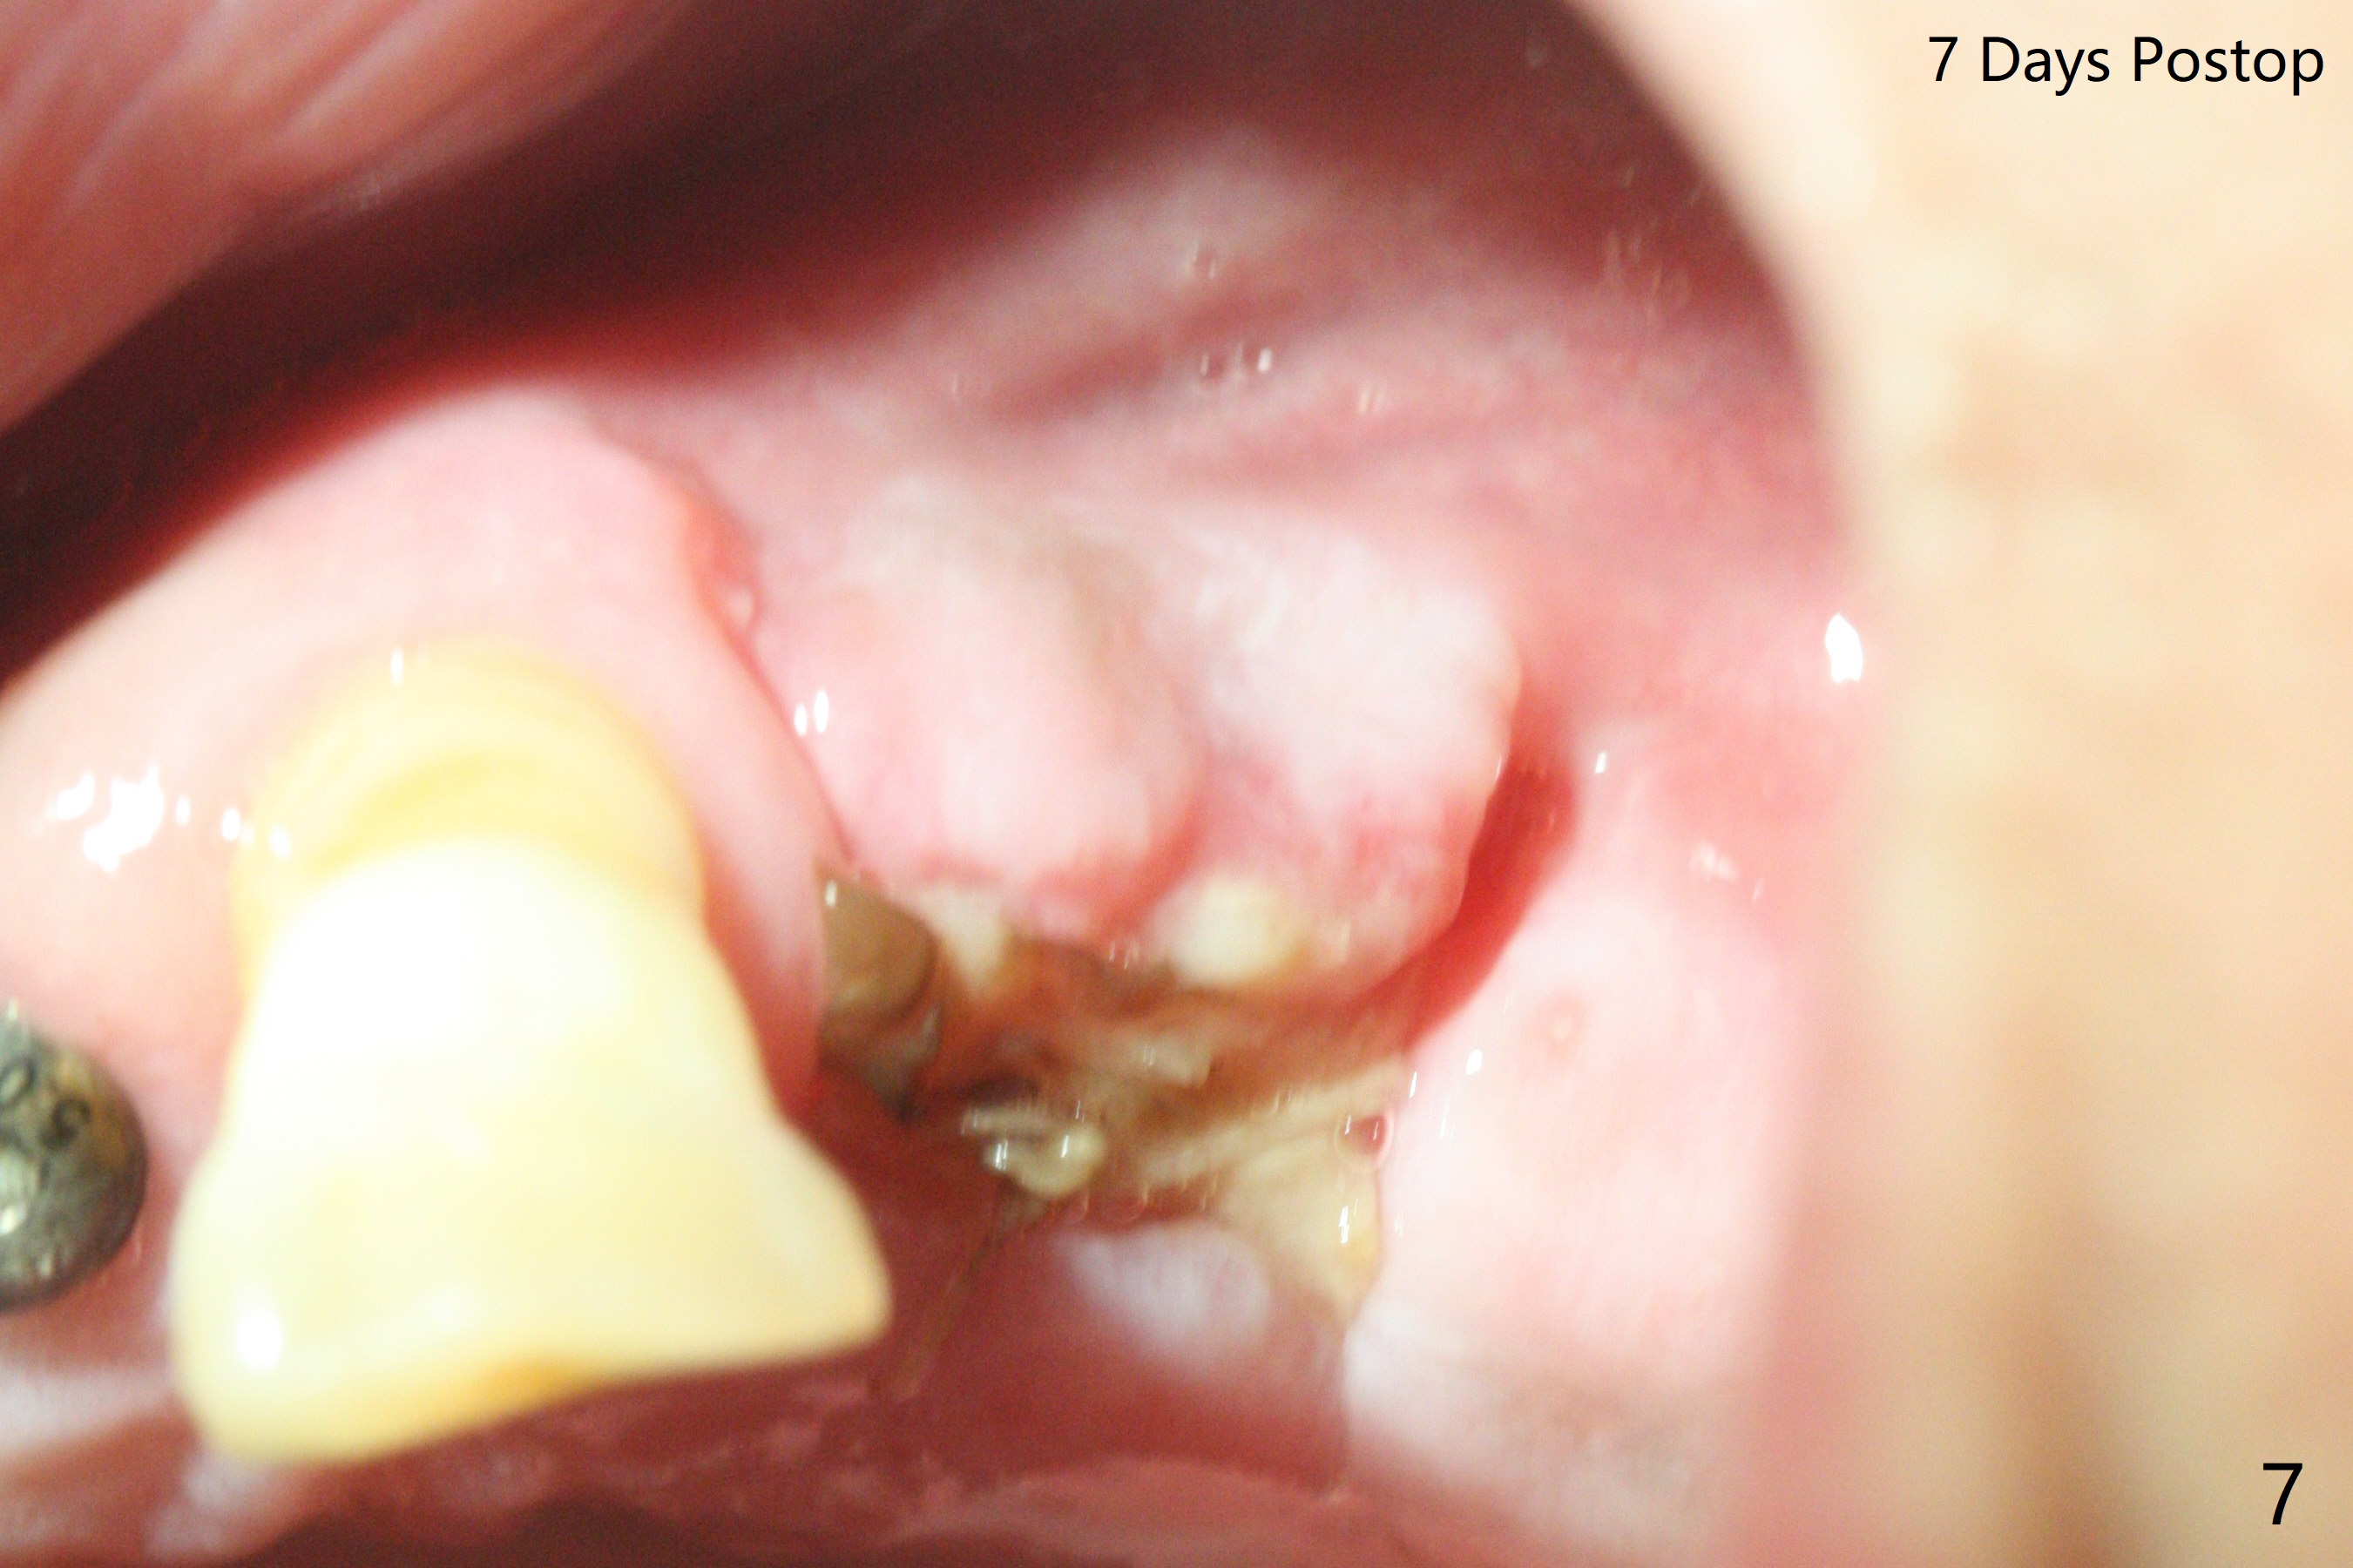

Five months post implant removal and bone graft, incision is made at #12. Osteotomy is being done with guide until 3.0x7.3 mm drill with 1 O-ring (palatal wall being thin), followed by 3.2x17-19 mm sinus round drills and 2.2x11.5 mm drill. After placement of 2 small loads of bone graft, a 4x9 mm dummy implant is inserted for sinus lift (Fig.1,2 *). By this time, the buccal plate is gone, while there is apparently the palatal periosteum. With more bone graft for sinus lift, a 4x9 mm final implant is placed with 30 Ncm (machine) and 4 mm subgingival (Fig.3,4 double arrows). Sticky bone (Fig.5,6 *) is applied around the coronal end of the implant and cover screw (S), followed by 2 pieces of PRF and 4-0 PGA suture. The sutures appear to have been dissolved and PRF membrane exposed 7 days postop (Fig.7,8 (smoker)). Four months postop, the wound heals except a small hole, which seems to be communicated with the underlying implant (Fig.9). The sinus lift remains (Fig.10 <), while bone loss appears to be present around the implant (Fig10,11 *). After placement of 5.5x4 mm healing abutment and before suturing, allograft is pushed into periimplant space (Fig.12, 13 *).